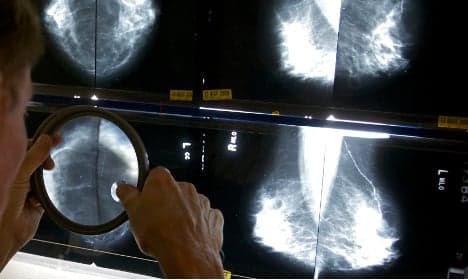

Breast cancer survival was 86 percent in Sweden, with a European average of 81.8 percent.

Breast cancer survival was 86 percent in Sweden, with a European average of 81.8 percent.